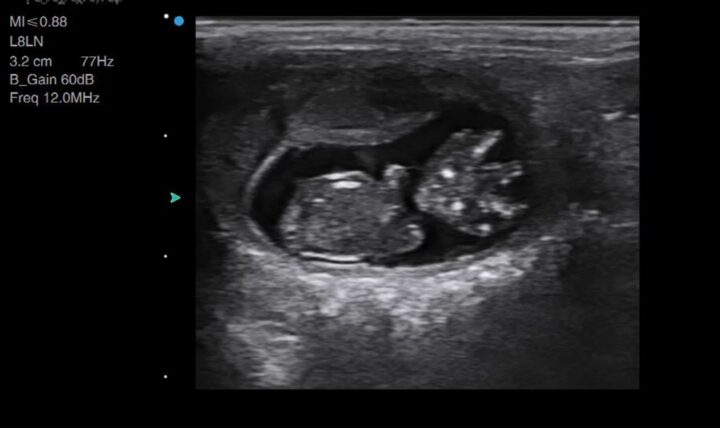

You will likely begin with your depth on its default setting or increased for larger breeds of dog. Once you find a gestation sac (Figure 1), you should optimise your image by reducing your depth and ensuring your focal point is at the level of the foetus. This will allow you to confirm the presence of a heartbeat.

More advanced users may begin to spot foetal abnormalities, such as hydrocephalus, foetal anasarca or bowel obstructions, due to the ease at which ultrasound can image fluid (Figure 4). This is a clear advantage of the veterinarian performing scans in-house over the lay scanner, who would need to refer such findings.